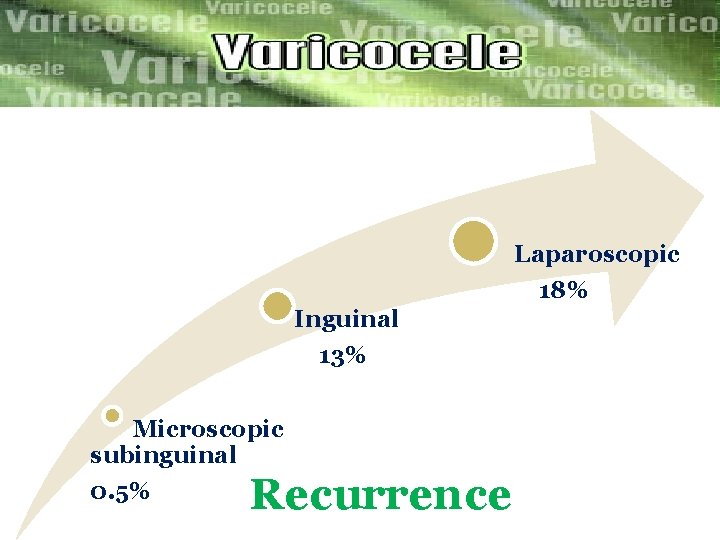

Laparoscopic 18% Inguinal 13% Microscopic subinguinal 0. 5% Recurrence